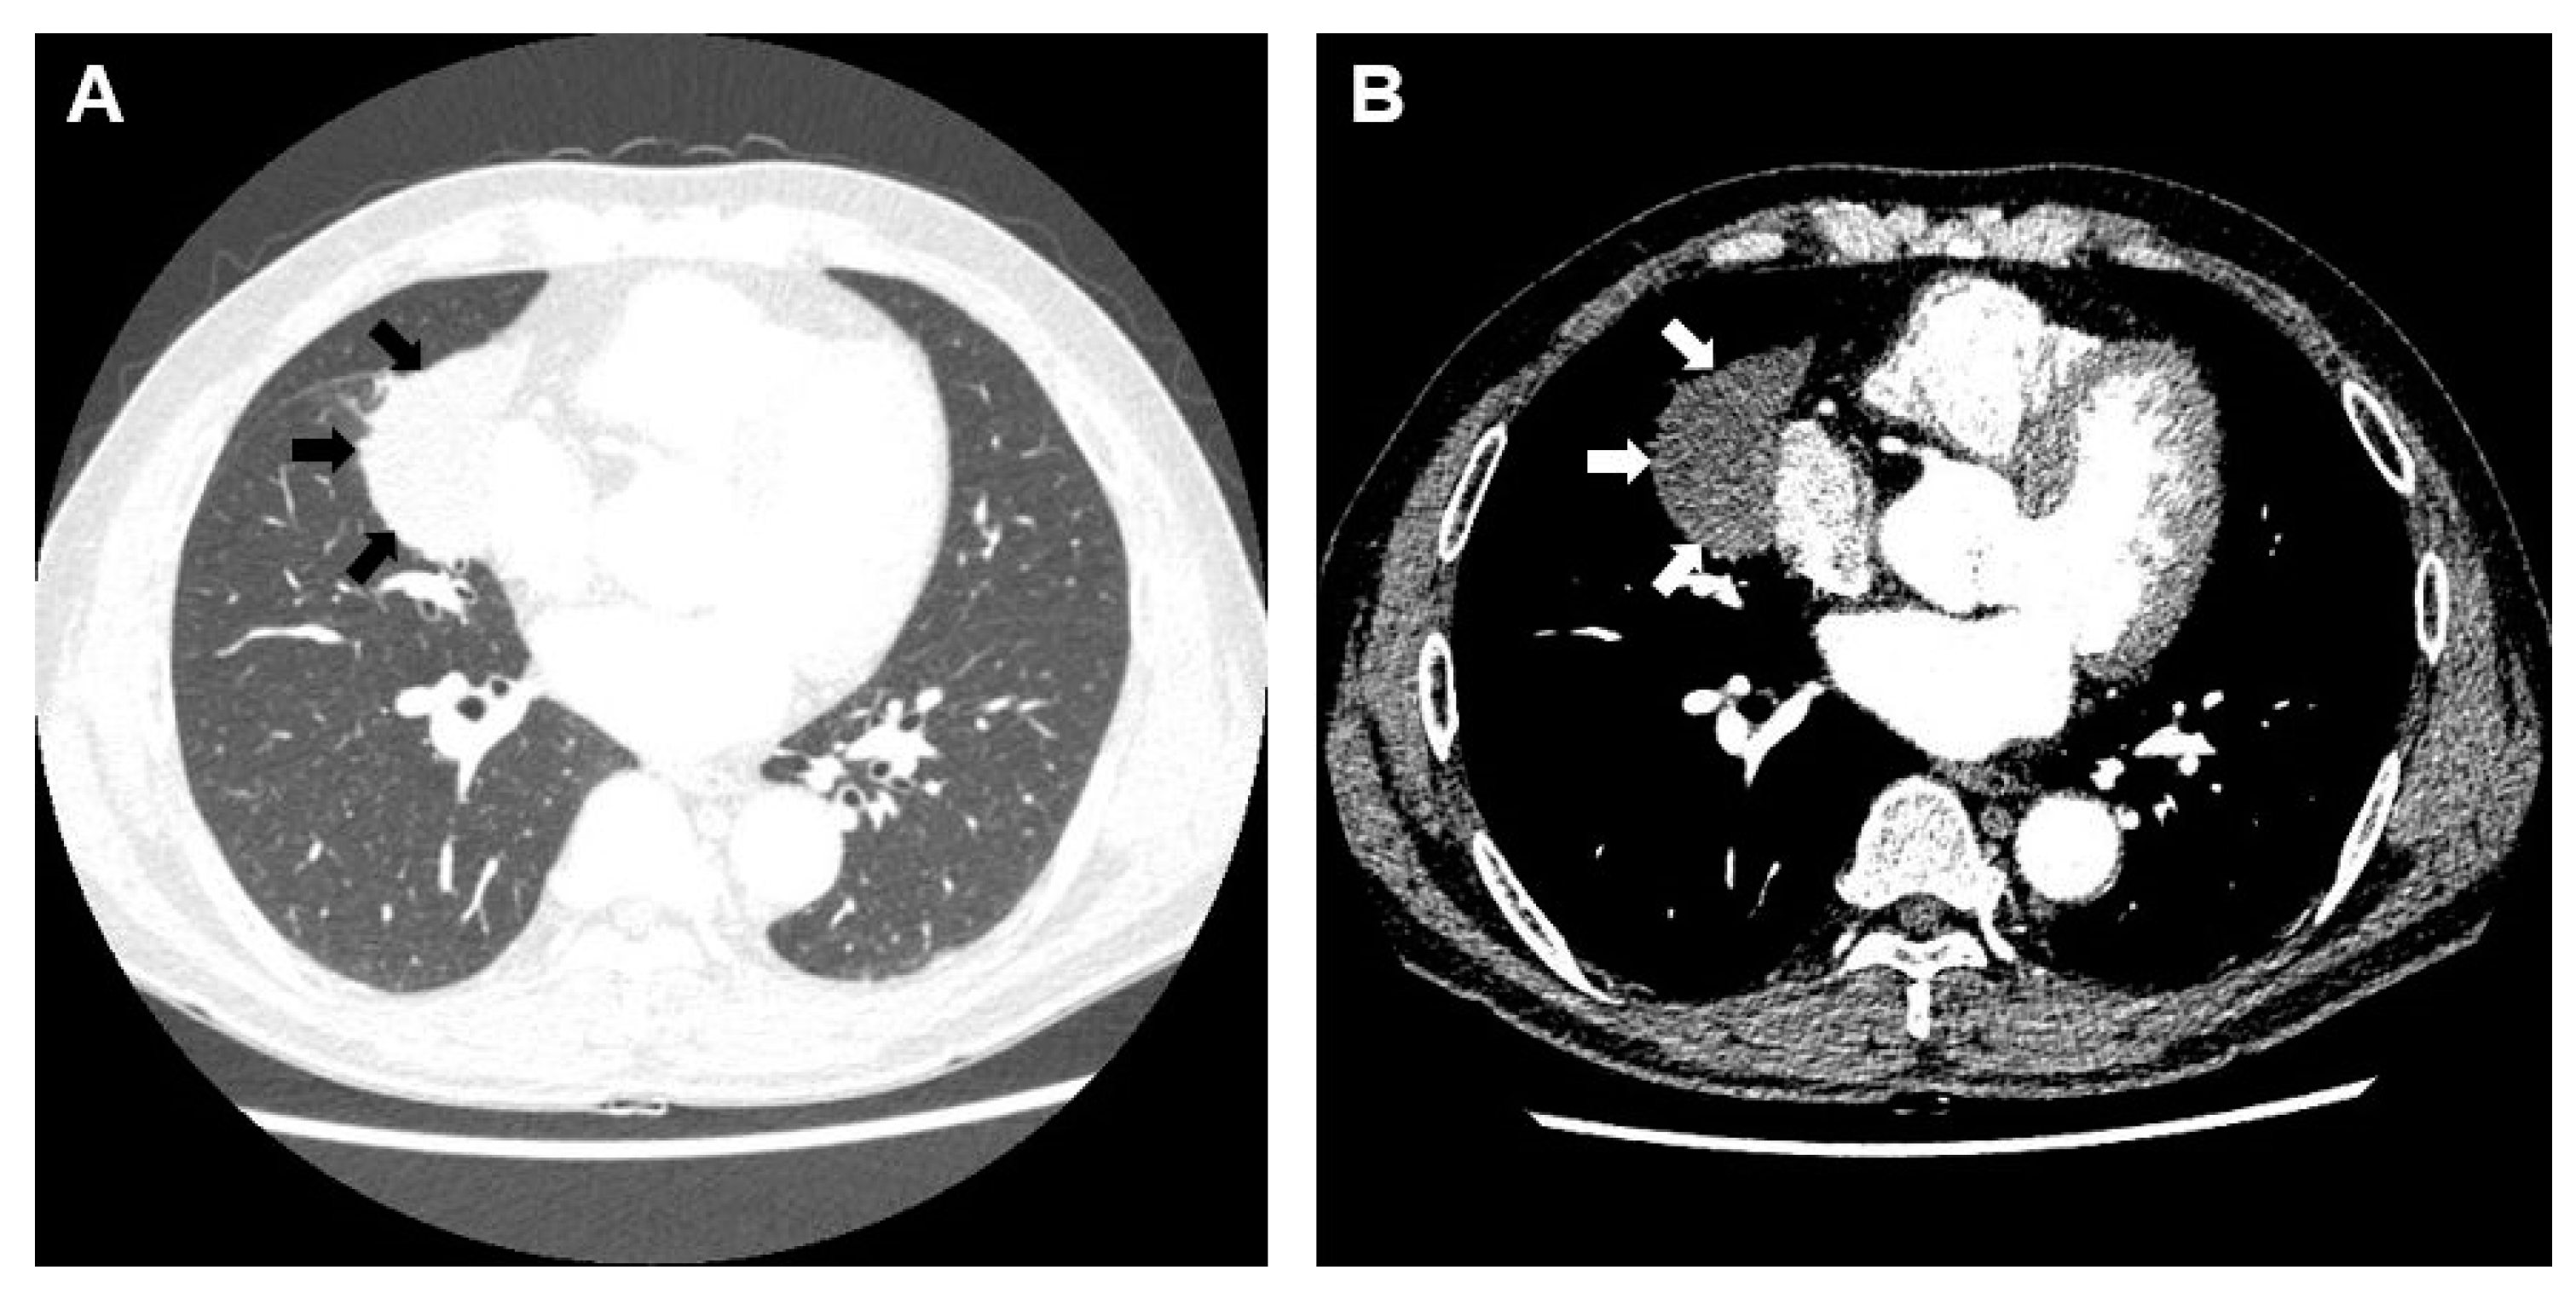

2. Case Presentation